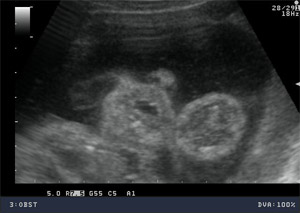

USG 3D / 4D

W nowoczesnych wysokiej klasy aparatach ultrasonograficznych istnieje możliwość przetwarzania danych z badania dwuwymiarowego co umożliwia pokazywanie obrazów trójwymiarowych badanych struktur płodu w czasie rzeczywistym.

Ultrasonografia trójwymiarowa 3D pozwala na uzyskanie statycznych obrazów przestrzennych, które otrzymywane są w procesie obróbki komputerowej danych z badania dwuwymiarowego. Ultrasonografia 4D pozwala na uwidocznienie dynamicznego przestrzennego obrazu.

Ta nowa prezentacja (prezentacja 4D) pochodzi od dodania czwartego wymiaru jakim jest czas. Badanie płodu metodą 4D pozwala nie tylko na obrazowanie przestrzenne płodu ale również pozwala na obserwację ruchów twarzy, obserwację otwierania i zamykania oczu, ruchów języka, ssania palców. Przy korzystnym ułożeniu płodu, w odpowiednim wieku ciążowym ( najlepiej pomiędzy 15. a 35. tygodniem ciąży) możliwa jest diagnostyka szeregu wad rozwojowych płodu. Badanie 4D pozwala też na precyzyjne obrazowanie rozwoju płodu i umożliwia podejrzenie wyglądu dziecka, którego wygląd jest niemal identyczny z jego rzeczywistym wyglądem.

Zastosowanie techniki 3D i 4D ma szczególne zastosowanie w położnictwie. Umożliwiają precyzyjną ocenę narządów wewnętrznych płodu, np. serca, mózgowia, kręgosłupa, twarzy oraz w sposób istotny pozwalają na zwiększenie wykrywalności wad budowy płodu .